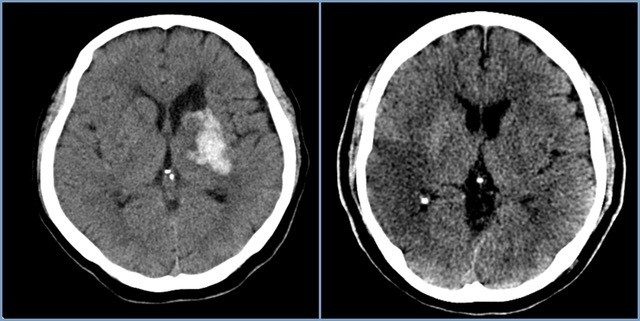

뇌혈관이 막히거나 터지는 질환을 부르는게 뇌졸중이고 그 중 뇌혈관이 막히는게 뇌경색 그리고 뇌혈관이 터지는 것을 뇌출혈이라고 합니다. 뇌졸중은 영구적인 손상이 많다고 하며 증상에 따라 전신이나 육체 일부 기능이 마비되는 등의 극심한 후유증이 남는 무서운 질병입니다 오늘은 뇌경색 초기증상에 대하여 알려드리도록 하겠습니다.

허혈성 뇌졸중은 발생 기전에 따라 대혈관 질환에 의한 뇌경색, 심인성 뇌경색 또는 심인성 뇌경색, 소혈관 질환 또는 틈새 뇌경색, 기타 드문 이유가 되는 것에 의한 뇌경색으로 나누어져요. 에피소드는 일정 기간 동안 증상이 완전히 가라앉는 경우입니다.

허혈성 뇌졸중의 대표적인 이유가 되는 것은 고혈압, 당뇨병, 고지혈증 등으로 인해서 뇌에 혈액을 전달하는 혈관에 동맥경화(동맥경화)가 발생하여 뇌로 가는 혈류를 차단하는 것입니다.